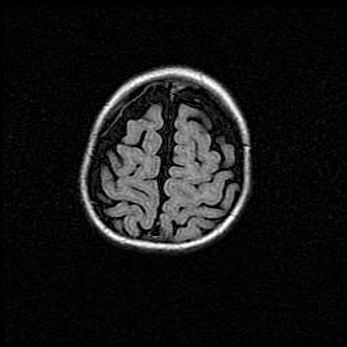

Сообщающаяся гидроцефалия. Кистозная энцефаломаляция головного мозга.

Возраст: 3 месяца 4 дня

Вес: 3100 г

Пол: женский

Окружность головы: 34 см

Срок гестации: 31 неделя

Кистозная энцефаломаляция головного мозга - одна из форм поражения головного мозга в детском возрасте. Характеризуется возникновением множественных и распространённых кист в коре, белом веществе и подкорковых образованиях головного мозга у плодов, новорождённых и детей раннего возраста. Развитие кистозной энцефаломаляции связано с внутриутробной асфиксией и гипотонией, родовой травмой, тромбозом синусов, пороками развития сосудов, инфекциями, сепсисом и другими причинами. Наиболее значимые инфекционные агенты: вирусы простого герпеса, цитомегалии, краснухи, токсоплазмы, энтеробактерии, золотистый стафилококк и другие.